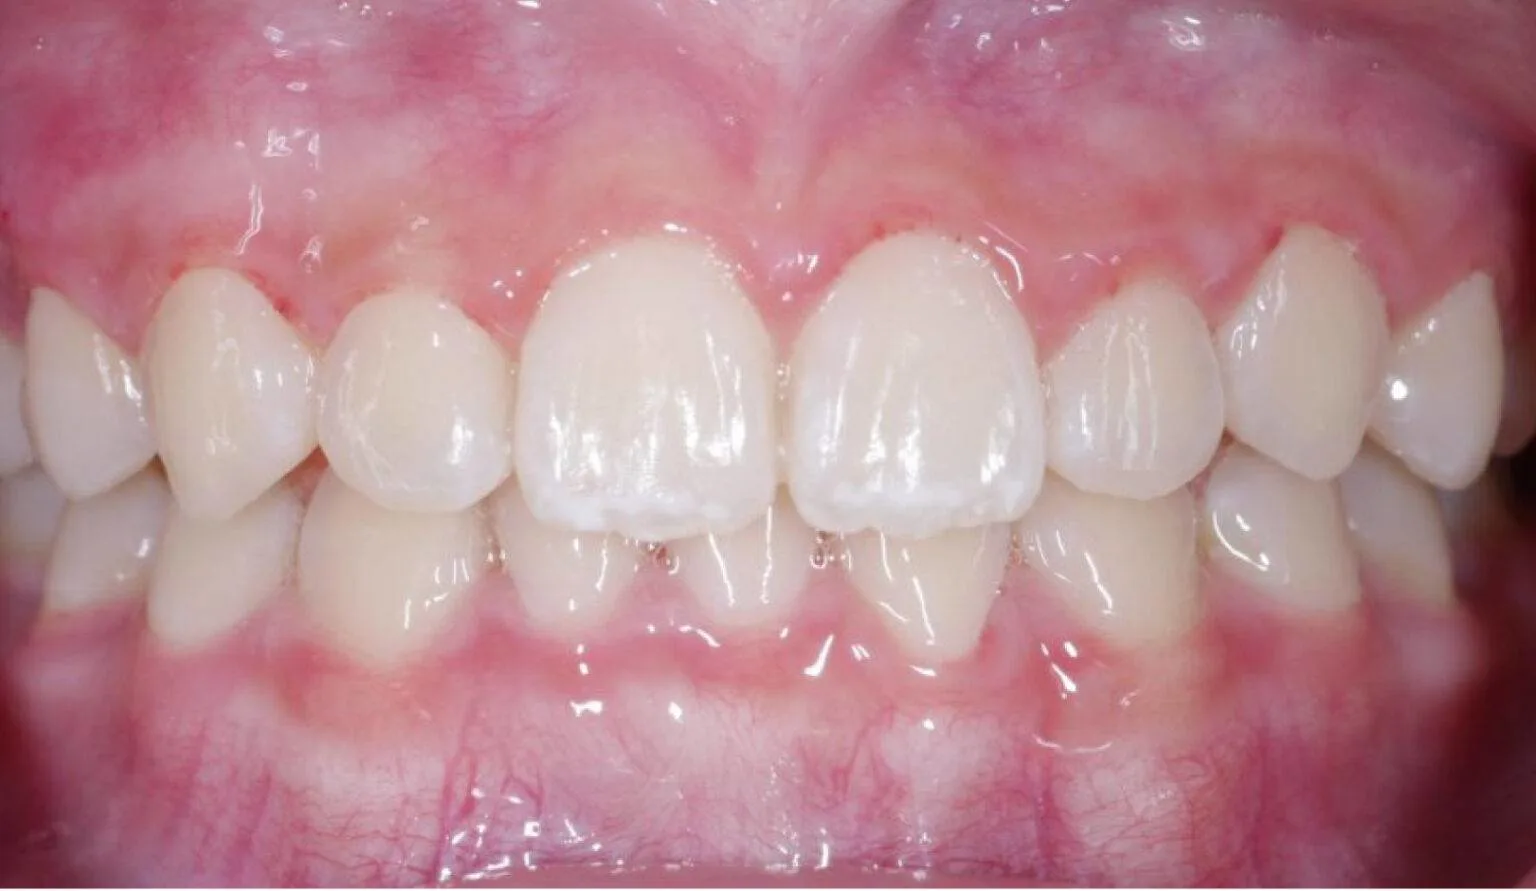

Before diastema treatment showing spacing between front teeth at SmileBox Clinic After diastema treatment showing closed spacing and aligned teeth at SmileBox Clinic